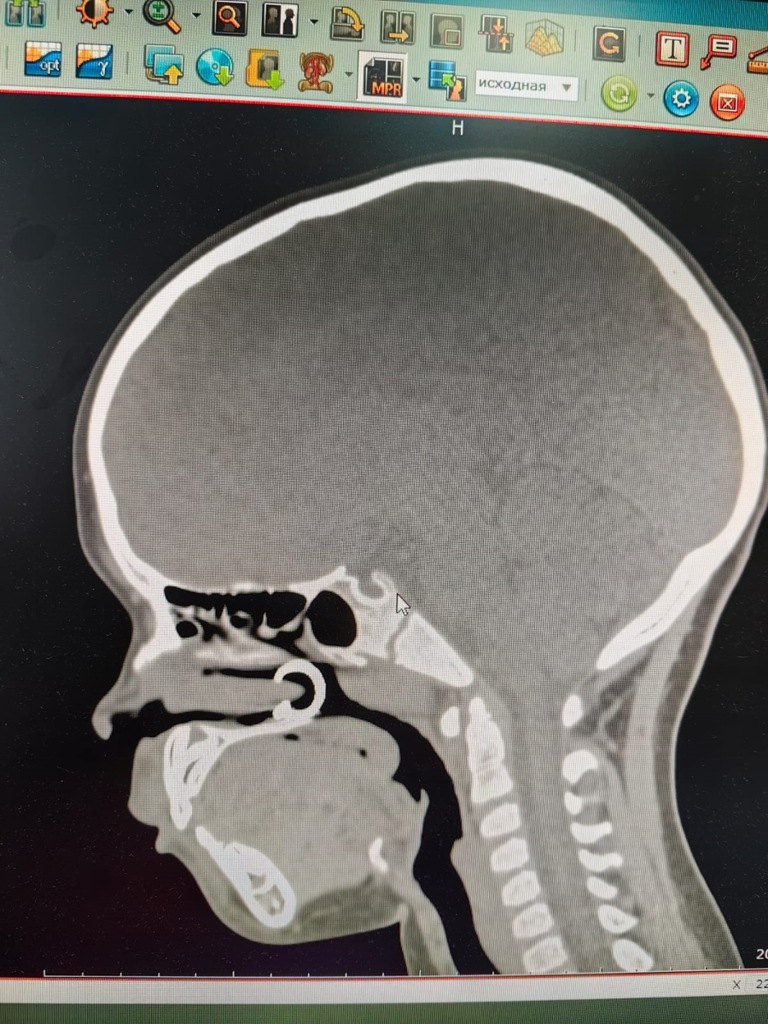

"К нам обратилась маленькая пациентка, которая вдохнула через нос сережку-пирсинг. Со слов родителей девочка решила повторить за своей старшей сестрой и надеть сережку на нос. После проведенного рентгенологического исследования была проведена эндоскопическая операция по удалению инородного тела. Все прошло успешно, и девочку отпустили домой", - рассказала врач-оториноларинголог Алена Фуфаева.